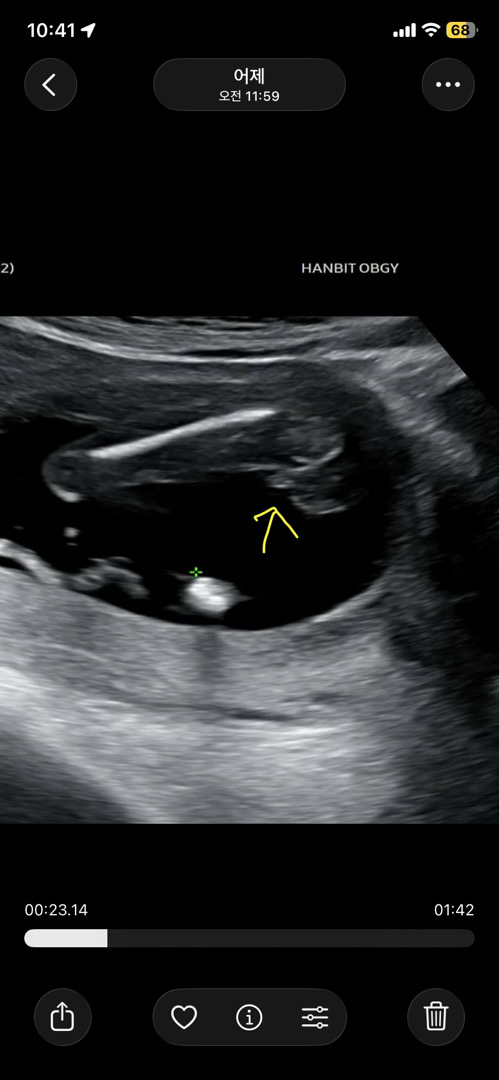

17주 초음파 아들?딸? 봐주세요!

선생님은 딸같다고 하셨는데 집와서 동영상 다시돌려보니 튀어나온게 있더라구요!? 탯줄일까욮?

아들은 .^. 요런모양으로 발끝향해잇어욤 보여주시능 사진은 꼭지점이 엉덩이쪽으로보여서 딸이라고 하신거같아여